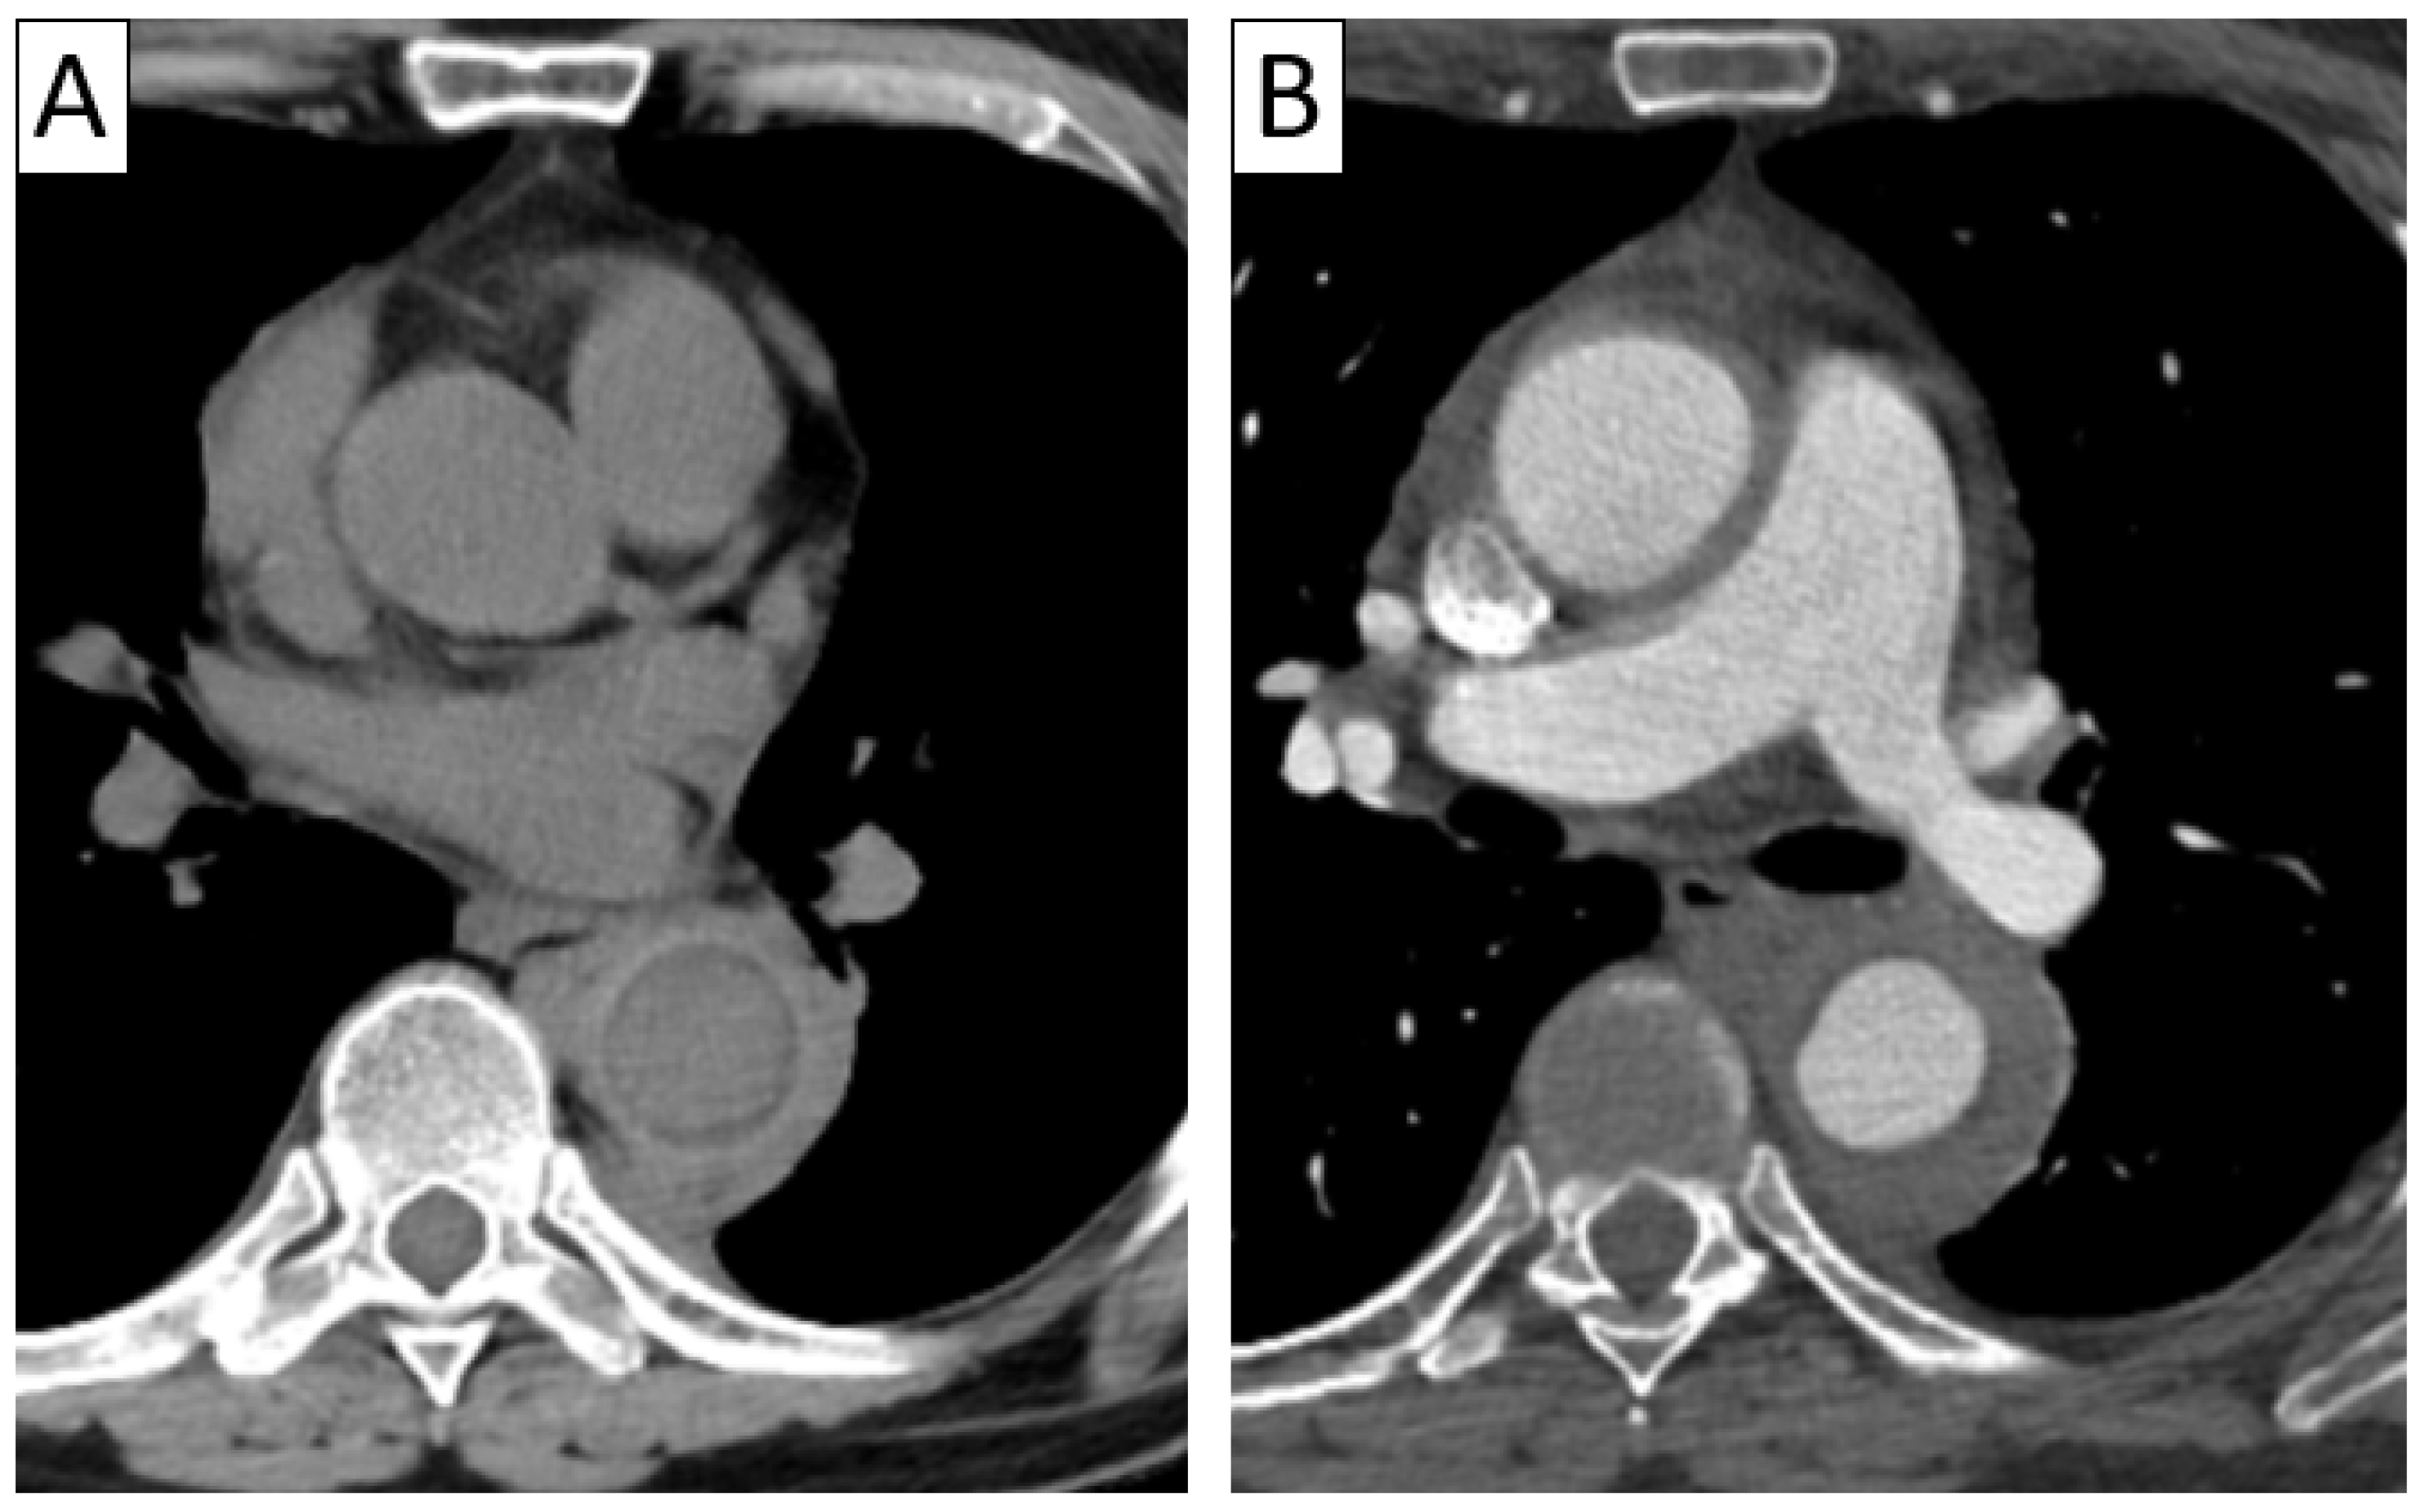

| CTA | Circumferential parietal thickening Vessel wall enhancement | Circumferential parietal thickening Vessel wall enhancement Luminal stenosis or narrowing |